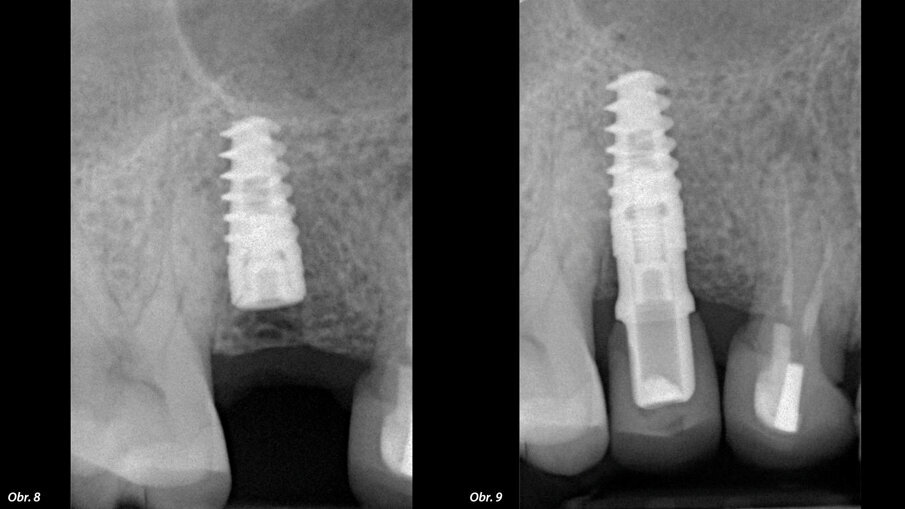

Dále byl použit Er:YAG laser s vlnovou délkou 2940 nm (LightWalker AT) opatřený digitálně kontrolovaným násadcem (X-Runner, Fotona) (obr. 4). Laser byl použit za parametrů 380 mJ a 20 Hz, působících v superkrátkých pulzech (50 mikrosekund). Byl použit externí zdroj sterilního fyziologického roztoku skladovaného při 5 °C v chladničce a tento roztok byl přiváděn pomocí peristaltické pumpy kvůli podpoře fototermické ablace a snížení teploty v místě zákroku. Digitálně kontrolovaný násadec umožňuje naprogramování a přesné provedení kruhové osteotomie o průměru 3,5 mm, tedy stejného průměru jako je poslední vrták dodávaný výrobcem implantátu. Během osteotomie byla pomocí milimetrové sondy kontrolována hloubka zavádění, až do dosažení předem nastavené hloubky 12 mm. Autor raději zavádí implantáty subkrestálně o 2 mm hlouběji, aby se předešlo resorpci v důsledku náklonu osy implantátu a bylo možno mít větší kontrolu nad emergence profilem náhrady. Byl zaveden kónický šroubový implantát vyrobený z titanu IV. třídy s opískovaným a kyselinou naleptaným povrchem (HELI, IDC). Implantát měl největší průměr 4,2 mm u vnějšího závitu a délku 10,0 mm. Po zavedení byl pomocí násadce Osstell (obr. 5, 6) určen kvocient stability implantátu (ISQ). Lalok byl sešit (obr. 7), byl pořízen RTG snímek (obr. 8) a stehy byly odstraněny po pěti dnech. V té době byl pacient požádán, aby zhodnotil pooperační bolest, kterou pociťoval, a to formou sdělení přiřazené číselné hodnoty od 0 do 10.

Klinická situace po zákroku.